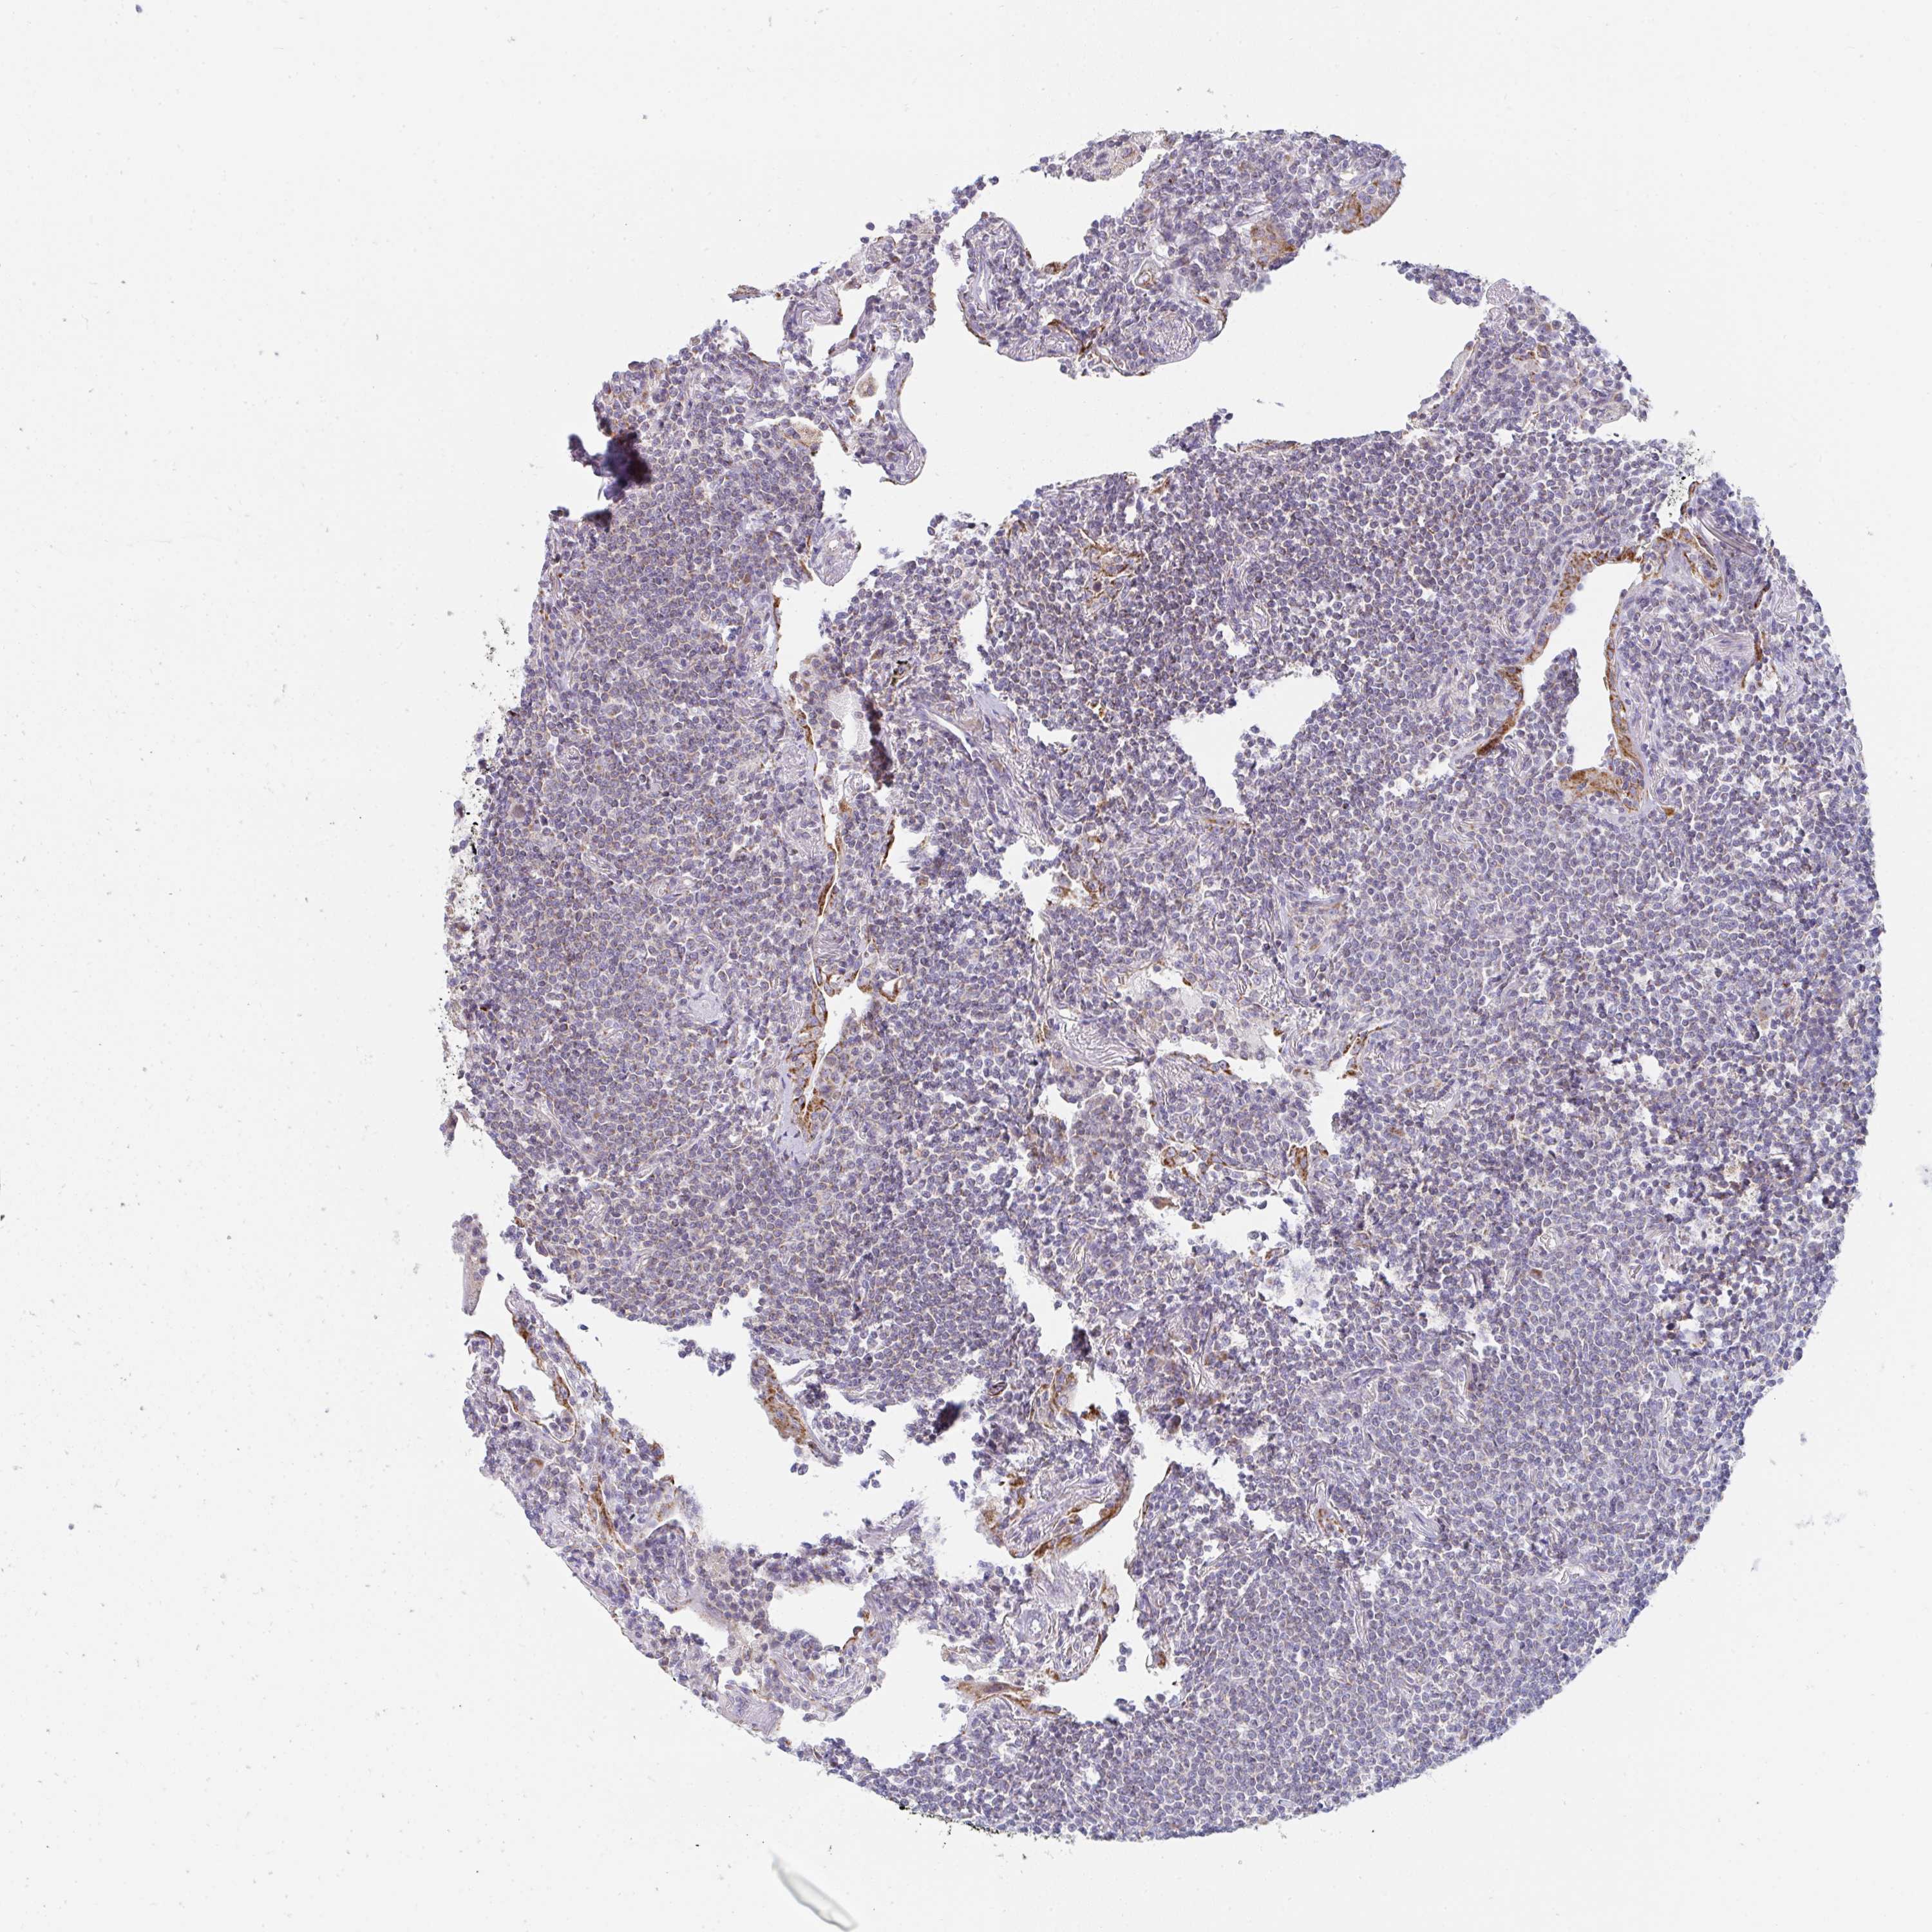

CANCER LYMPHOMA Show tissue menu

LYMPHOMA - Protein expressioni

A mouse-over function shows sample information and annotation data. Click on an image to view it in a full screen mode. Samples can be filtered based on level of antibody staining by selecting one or several of the following categories: high, medium, low and not detected. The assay and annotation is described here.

Antibody stainingi

Antibody staining in the annotated cell types in the current human tissue is reported as not detected, low, medium, or high, based on conventional immunohistochemistry profiling in selected tissues. This score is based on the combination of the staining intensity and fraction of stained cells.

Each image is clickable and will lead to virtual microscopy that enables deeper exploration of all samples and also displays staining intensity scores, fraction scores and subcellular localization as well as patient and tissue information for each sample.

Antibody HPA043226

Malignant lymphoma, non-Hodgkin's type, Low grade

Malignant lymphoma, non-Hodgkin's type, High grade

Hodgkin's disease, NOS